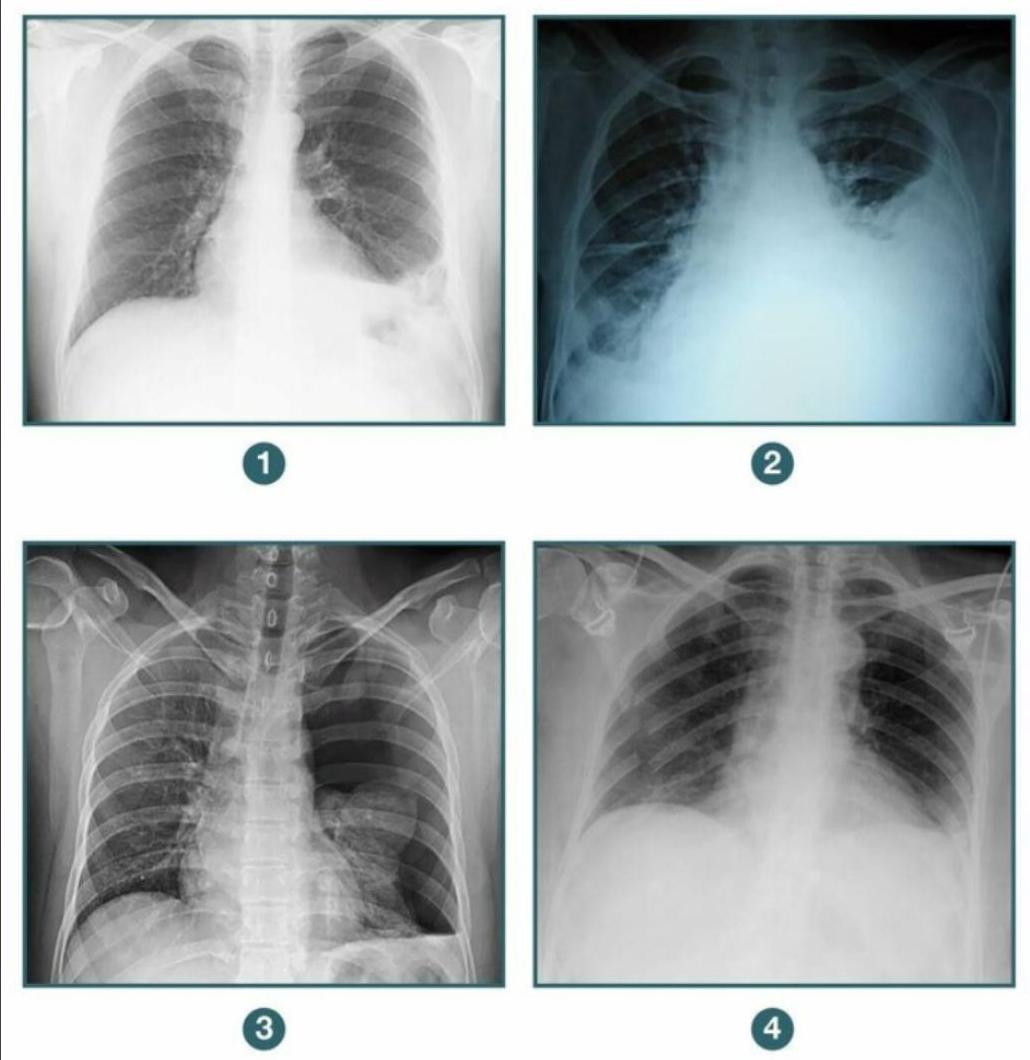

A patient presents to the casualty following blunt trauma to the chest. A chest X-ray was done. Among the following radiographs, in which case would you further evaluate the patient before putting a chest tube? 1. Diaphragmatic hernia 2. Hemothorax 3. Pneumothorax 4. Flail chest

Explanation: ***Correct Option: Diaphragmatic hernia*** - A **diaphragmatic hernia** (showing elevated hemidiaphragm with loops of bowel in the hemithorax) requires **further evaluation before chest tube placement** - **CT scan with contrast** or **nasogastric tube with X-ray** should be performed to delineate the anatomy and confirm herniated abdominal contents - **Chest tube placement is contraindicated** or requires extreme caution as it could perforate herniated abdominal organs (stomach, bowel, liver, spleen) - This condition requires **surgical repair**, not chest drainage - The key principle: **Always evaluate thoroughly before intervention when diaphragmatic injury is suspected** *Incorrect Option: Pneumothorax* - A **pneumothorax** (characterized by absence of lung markings in the periphery and visceral pleural line) has a straightforward indication for chest tube - **Chest tube is the definitive management** for significant or symptomatic pneumothorax to re-expand the lung - No additional evaluation needed before chest tube placement in hemodynamically stable patients with confirmed pneumothorax *Incorrect Option: Hemothorax* - A **hemothorax** (showing opacification in the lower lung field with blunting of costophrenic angle and fluid level) has a clear indication for chest tube - **Chest tube is indicated** to drain blood, relieve lung compression, and monitor for ongoing bleeding - Immediate chest tube placement is appropriate once diagnosed *Incorrect Option: Flail chest* - A **flail chest** (multiple rib fractures in two or more places creating unstable chest wall segment) primarily requires **pain management and ventilatory support** - A chest tube is **not indicated for flail chest itself** unless there is an associated pneumothorax or hemothorax - If flail chest is isolated, you would not place a chest tube at all, making this option incorrect for the question asked